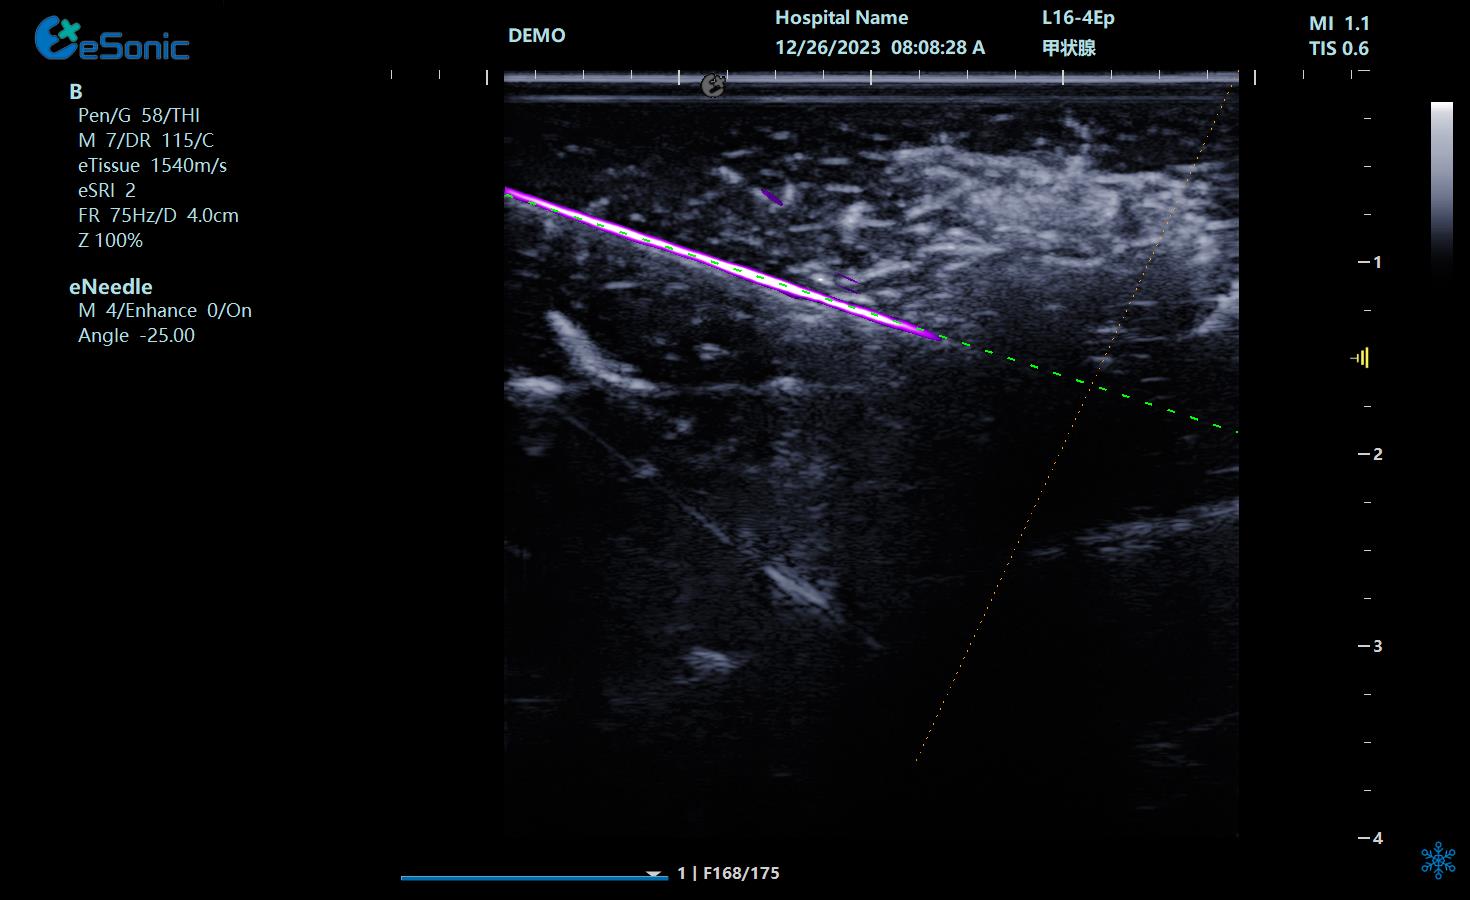

独家智能介入解决方案,实时引导介入治疗,更精准,更安全。

穿刺针增强